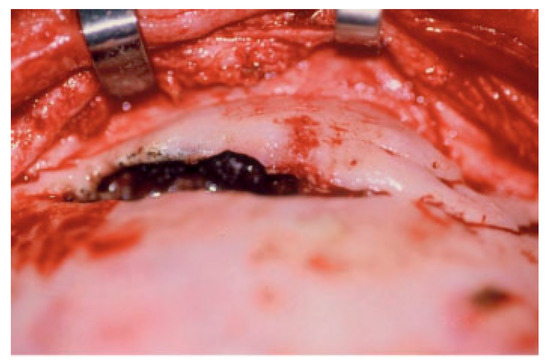

Disruption of the nasofrontal ostia or ducts is an important factor in the development of immediate and delayed complications after frontal sinus fractures (Figure 2) [8]. Combined fractures of the anterior and posterior table are almost always accompanied by injuries to the nasofrontal orifices [4,5,8]. Severity of the injuries is variable but can be predicted from the sinus wall fracture pattern and the mechanism of injury [4,8]. High-resolution computed tomography (CT) scanning as well as image-guided endoscopy can give sufficient information to predict a disruption of the drainage system, but there is nothing as good as direct visualization of the nasofrontal ostia [2,9,10]. Functional status can be estimated with fluorescein endoscopy; however, this may not always be accurate [3,10,11,12]. Successful management of frontal sinus fractures depends on correct diagnosis of structural pathology, which may lead to inflammatory or infectious complications. When in doubt, it is better to separate the anterior skull base from the nasal cavity. We believe this is best accomplished with vascularized tissue (Figure 3) [2,13,14].

Figure 2.

Intraoperative photograph of anterior and posterior wall frontal sinus fractures with no CSF leak and destruction of the nasofrontal ostia (drainage system).